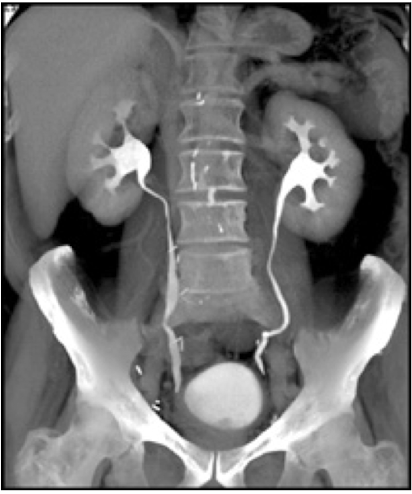

CT urography

CT scan using an IV contrast material to assess kidney, ureters, and bladder

Abdominal Radiograph

CT urogram

Which imaging is used to visualize ureteral stricture?